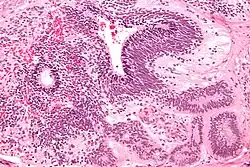

A micrograph view of dysgerminoma, showing actively dividing lobulated nuclei.

Dysgerminomas are comparable to testicular seminomas and account for approximately 32- 37% of all OGCTs.[1] They are particularly prominent in individuals with dysgenic gonads of 46, XY pure gonadal dysgenesis patients.[1] Based on gross examinations, dysgerminomas are characterized by having a ‘solid, lobulated, tan, flesh-like gross appearance with a smooth surface'.[1] Microscopically, the cellular structure is distinguished by a round-ovoid shape containing ample eosinophilic cytoplasm and an irregularly shaped nuclei.[1] The uniformly positioned cells are separated through the fibrous strands and lymphocytic infiltration is commonly observed.[4]